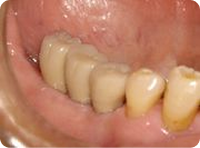

施術例④

治療前

右下の奥歯3本が欠損しています。

治療後

3ヵ月後、インプラントの土台にセラミック冠をかぶせました。見た目も天然の歯とほぼ変わらず自然な仕上がりとなり、しっかりと物を噛む事ができる様になりました。